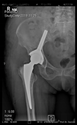

The radiological examination allowed us to verify the close bone-to-implant contact and the unchanged position of the implant during follow-up.

In all the cases operated with the above-described targeting procedure, the stems of the cups remained between the cortical bone surfaces without perforation of the linea terminalis, as shown by postoperative radiographs. There were no complicated surgical situations. In 16 cases, the wound healings were uneventful, and the hips were able to bear weight again after postoperative rehabilitation.